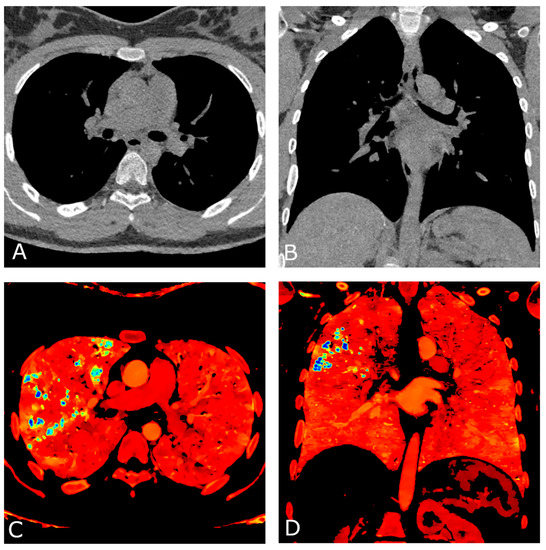

2. Case Report